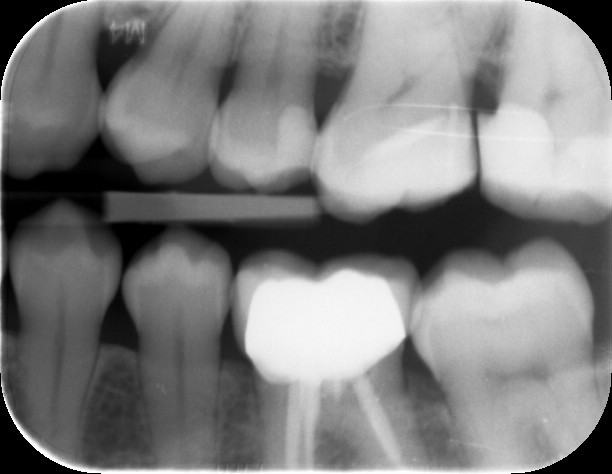

Dit zijn de foto's die ik heb

Je hebt wel een overbelasting en de wortels zijn wat kort.

Heb je een beugel gehad? Lijkt alsof er toch teveel krachten op je voortanden komen.

Je tanden kunnen inderdaad weer aan de wandel gaan na het beugelen en toch weer gaan storen in de articulatie/occlusie (dus manier van dichtbijten, schuiven enz) en dus toch overbelast raken. De overbelasting is zichtbaar als een 'verbrede parodontaal spleet' tussen je tanden en je bot. Verder zie ik toch wel een beetje botverlies, met name bij een kies waarvan de vulling overstaat. Hier blijft te veel plak en voedsel hangen. Ik zou toch eens een second opinion aanvragen bij iemand die wat meer verstand heeft van de belasting. Misschien eens terug naar de orthodontist?

Betreft dat de kies naast de kies met wortelkanaalbehandeling op de onderste foto?